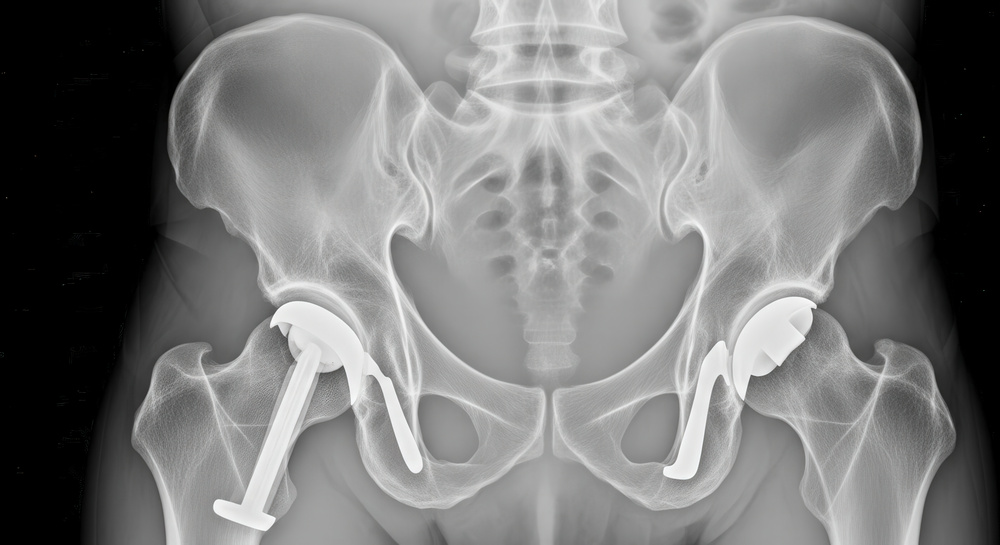

A artroplastia total do quadril (ATQ) é amplamente reconhecida como uma das cirurgias mais bem-sucedidas da Ortopedia moderna, com alto índice de satisfação e melhora funcional duradoura. Com o aumento da demanda por recuperação rápida e retorno precoce às atividades, especialmente em pacientes mais jovens e ativos, a via anterior direta (Direct Anterior Approach – DAA) tem ganhado destaque como alternativa às abordagens cirúrgicas convencionais, como a posterior ou lateral.

Ao fim, um total de 17 metanálises foram incluídas, publicadas entre 2013 e 2025, envolvendo 1.575 pacientes, sendo 785 pacientes submetidos à DAA e 790 pacientes no grupo das abordagens tradicionais (320 pacientes de abordagem lateral, 470 pacientes com acesso posterior). Desfechos como dor, função, tempo cirúrgico, sangramento, tempo de internação e complicações pós-operatórias foram avaliados. A qualidade metodológica das metanálises foi avaliada com a ferramenta AMSTAR 2.